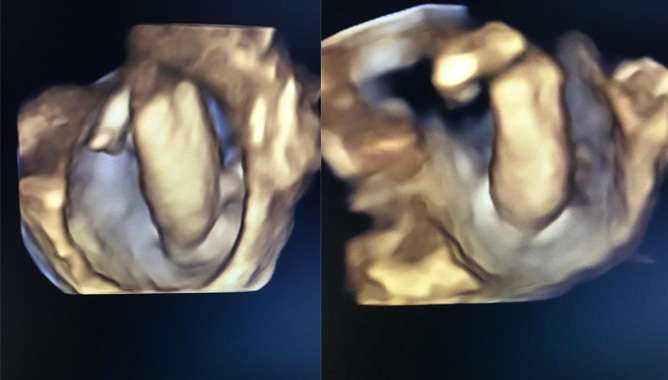

വയറിന് ഒരു തടിപ്പുണ്ട് എന്ന് മാത്രമാണ് പറഞ്ഞത്. ഉടന് തന്നെ സ്കാനിങ് ചെയ്തുനോക്കി. ആ ഘട്ടത്തില് ലിവറിനും കിഡ്നിക്കും ഇടയില് ഒരു ഫ്ളൂയിഡ് കണക്ഷനും കൈയും തലയും കാലും ഏതെന്ന് മനസിലാവാത്ത മറ്റൊരു അവയവും കണ്ടു. അപ്പോള് തന്നെ അതിന്റെ ത്രിഡി സ്കാനിങ് ചെയ്തു. അതിന്റെ ഇമേജുകളെല്ലാം പരിശോധിച്ചപ്പോഴാണ് ഇത് ഫീറ്റസ് ഇന് ഫീറ്റു എന്ന എക്സ്ട്രീമിലി റെയര് കണ്ടീഷനാണെന്ന് മനസിലാകുന്നത്. അങ്ങനെ ആ റിപ്പോര്ട്ടുമായി അവര് കോഴിക്കോട് മെഡിക്കല് കോളേജില് എത്തുകയായിരുന്നു.

കേരളത്തില് ആദ്യമായി ഇത്തരമൊരു രോഗാവസ്ഥ ഡയഗ്നോസ് ചെയ്യുന്നത് ഡോ. ഹരിയാണ്. ഫീറ്റസ് ഇന് ഫീറ്റുവിന്റെ ത്രിഡി ഇമേജുകളൊന്നും ഇതുവരെ ആര്ക്കും ലഭ്യമായിരുന്നില്ല.